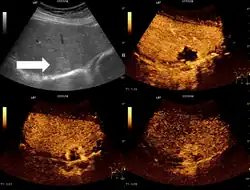

In den meisten Fällen werden Leberhämangiome im Rahmen einer Abdomensonographie diagnostiziert, oft als Zufallsbefund. Sie stellen sich dort als rundliche bis ovale, scharf begrenzte, echoreiche Strukturen dar. In der Duplexsonographie kann mitunter ein zuführendes Gefäß dargestellt werden.[1] Eine sichere Diagnose kann mittels Kontrastmittelsonographie erreicht werden: hier zeigt sich eine zentripetale Füllung (von außen nach innen) des Hämangioms mit Kontrastmittel.[2] Im deutschen Sprachraum wird dies auch als Irisblendenphänomen bezeichnet. Ebenso ist eine Diagnose mittels CT oder MRT möglich.